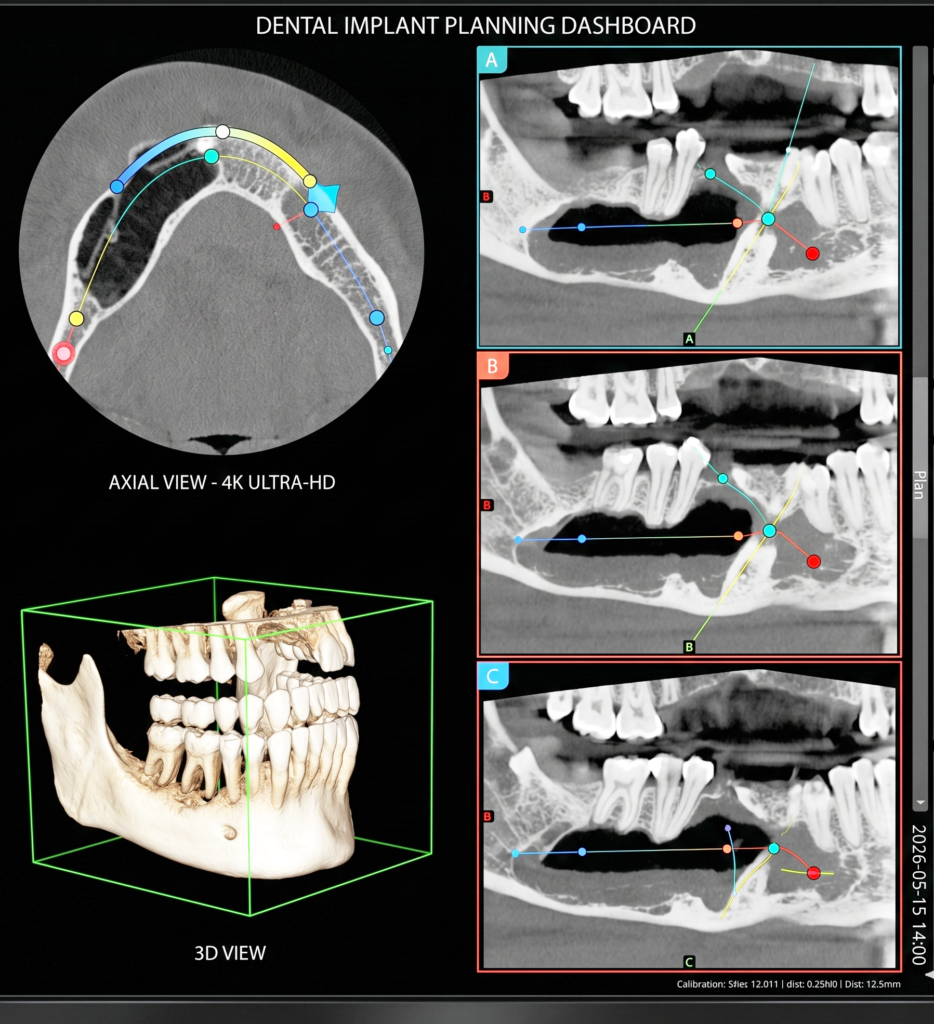

Advanced CBCT & Dental Imaging Services provide precise, high-resolution 3D scans for accurate diagnosis and treatment planning. Using modern technology, we ensure fast, reliable results with minimal radiation exposure. Our expert team focuses on patient comfort, delivering safe, efficient imaging solutions to support dentists in achieving better clinical outcomes.

He is certified in Cone Beam Computed Tomography (CBCT) and has extensive experience in advanced radiological diagnosis. Dr. Singh is associated with several reputed centers across India as a consultant radiologist for CBCT reporting. His expertise includes implant planning, impacted teeth localization, oral and maxillofacial pathology interpretation, TMJ assessment, maxillary sinus evaluation, and airway analysis.